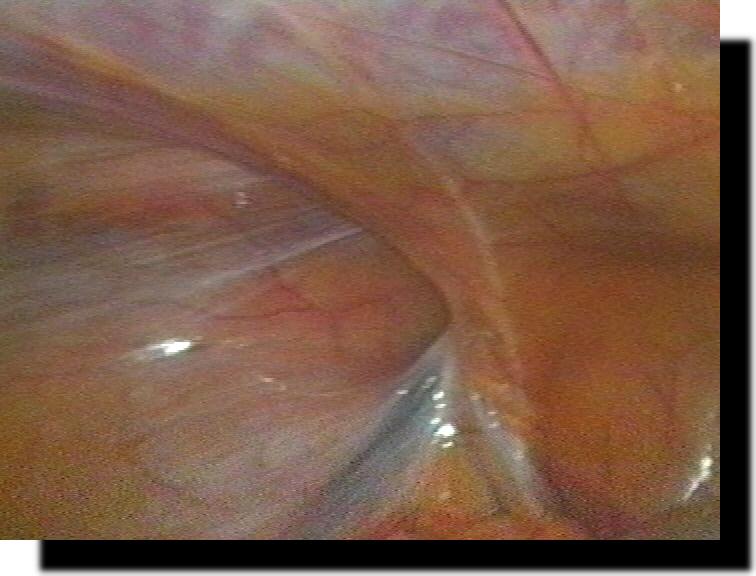

normale "unschuldige" Appendix